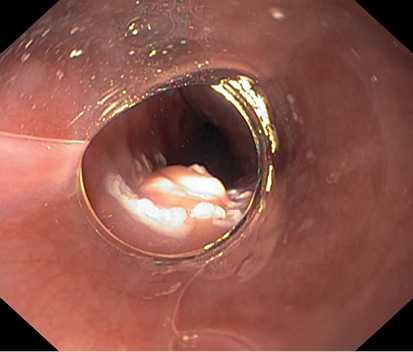

По данным ЭГДС, выполненной при поступлении: на фоне недостаточности кардии и неэрозивного рефлюкс-эзофагита на уровне 33 см от резцов по заднеправой стенке пищевода расположено экзофитное новообразование полиповидной формы размером 8×5 мм белесой окраски, выступающее в просвет на 4—5 мм, симптом шатра отрицательный (рис. 1, 2). Поверхность новообразования гладкая, сосудистый рисунок прослеживается.

Рис. 1. Новообразование по заднеправой стенке пищевода. Фото авторов.

Рис. 2. Новообразование по заднеправой стенке пищевода. Фото авторов.